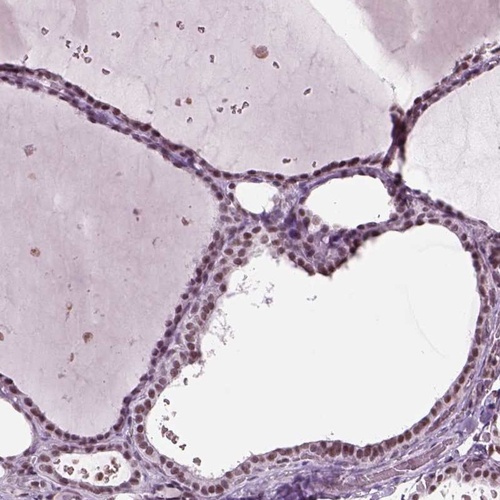

Immunohistochemical staining of human thyroid gland shows moderate nuclear positivity in glandular cells.